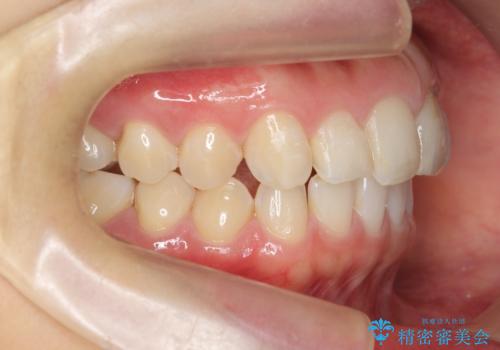

出っ歯に見える前歯の改善 部分ワイヤーとマウスピース矯正

- 出っ歯に見える前歯の改善を希望され、来院されました。

マウスピースでは改善の難しい歯の動きを部分ワイヤー矯正で整えたのち、奥歯の噛み合わせや細かい歯の並びをマウスピース矯正インビザラインで整えていきます。

最終的な前歯の並びに大変満足いただくことができました。